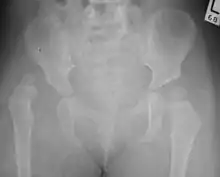

Дисплазія кульшового суглоба, діагностована за допомогою УЗД[41] та проекційної рентгенографії («рентген»)[42]. Зазвичай ультразвукова візуалізація є бажаною до 4 місяців через обмежене окостеніння скелета[40][notes 1].

Незважаючи на широке поширення ультразвуку, рентген малого тазу все ще часто використовується для діагностики або моніторингу дисплазії кульшового суглоба або для оцінки інших вроджених станів або пухлин кісток[43]. Найбільш корисні лінії та кути, які можна провести в дитячому тазі для оцінки дисплазії кульшового суглоба, такі: (У дорослих застосовують інші виміри!)